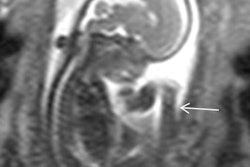

"When fetal brain abnormalities are suspected on ultrasound, in utero MR imaging is able to contribute significantly to the diagnostic pathway by both clarifying findings and increasing significantly the detection rate of abnormalities, particularly in midline and posterior fossa anomalies," they wrote (European Radiology, 21 September 2016).

Ultrasound and MRI differed the most in regard to diagnosing midline abnormalities, particularly the posterior fossa, with MRI able to better detect abnormalities in the region.